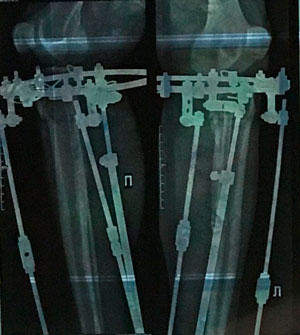

Исходник - 50 лет.

Дата операции - 30.07.2019г.